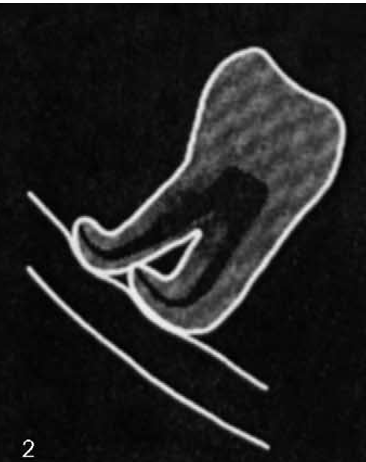

Q

Narrowing of inferior dental canal